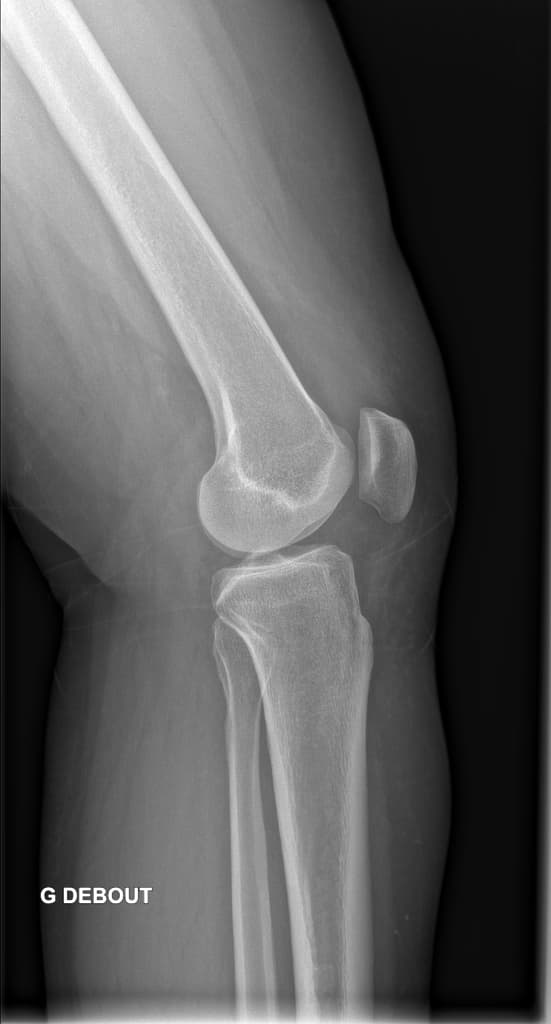

Bucket Handle Meniscal Tear of the Medial Meniscus (Vết rách sụn chêm dạng xô gánh)